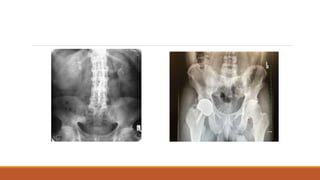

In established AS radiographs show SI joint irregularity, widening of joint spaces and fusion of

bones.

In advanced cases ossification of the anterior longitudinal ligament and facet joint may be

visible.(appearance of bamboo spine)

Erosive changes might be seen in ischial tuberosity ,pubis symphysis and peripheral joints

Later on osteoporotic changes can be seen

Patients may have normal x-rays in early stages

Investigations In established ASradiographs show SI joint irregularity, widening of joint spaces and fusion of bones. In advanced cases ossification of the anterior longitudinal ligament and facet joint may be visible.(appearance of bamboo spine) Erosive changes might be seen in ischial tuberosity ,pubis symphysis and peripheral joints Later on osteoporotic changes can be seen Patients may have normal x-rays in early stages MRI is preferred if clinical suspension of AS ESR and CRP may be raised HLA-b27 testing should be done showing clinical features of AS